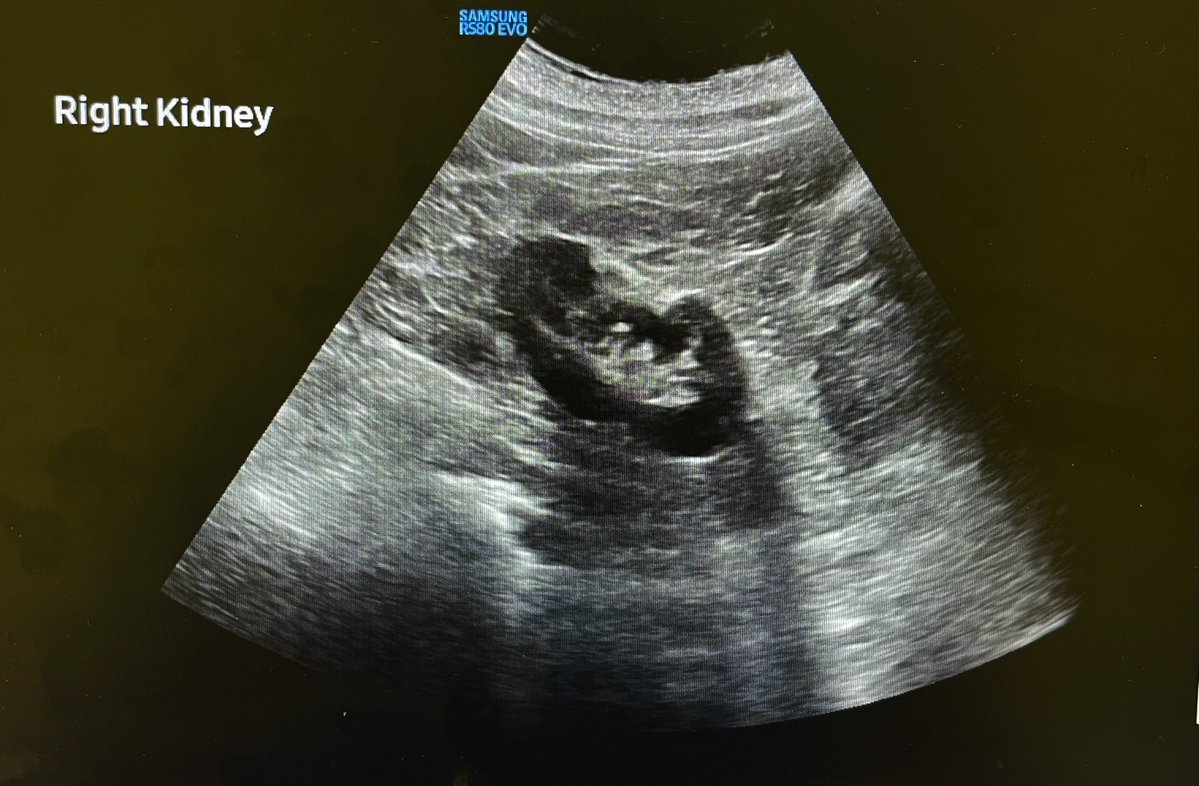

54F with right flank pain and haematuria. Solid heterogeneous right renal mass with vascularity. ? Renal cell carcinoma. @Rad_Munagi @AjuboDaso